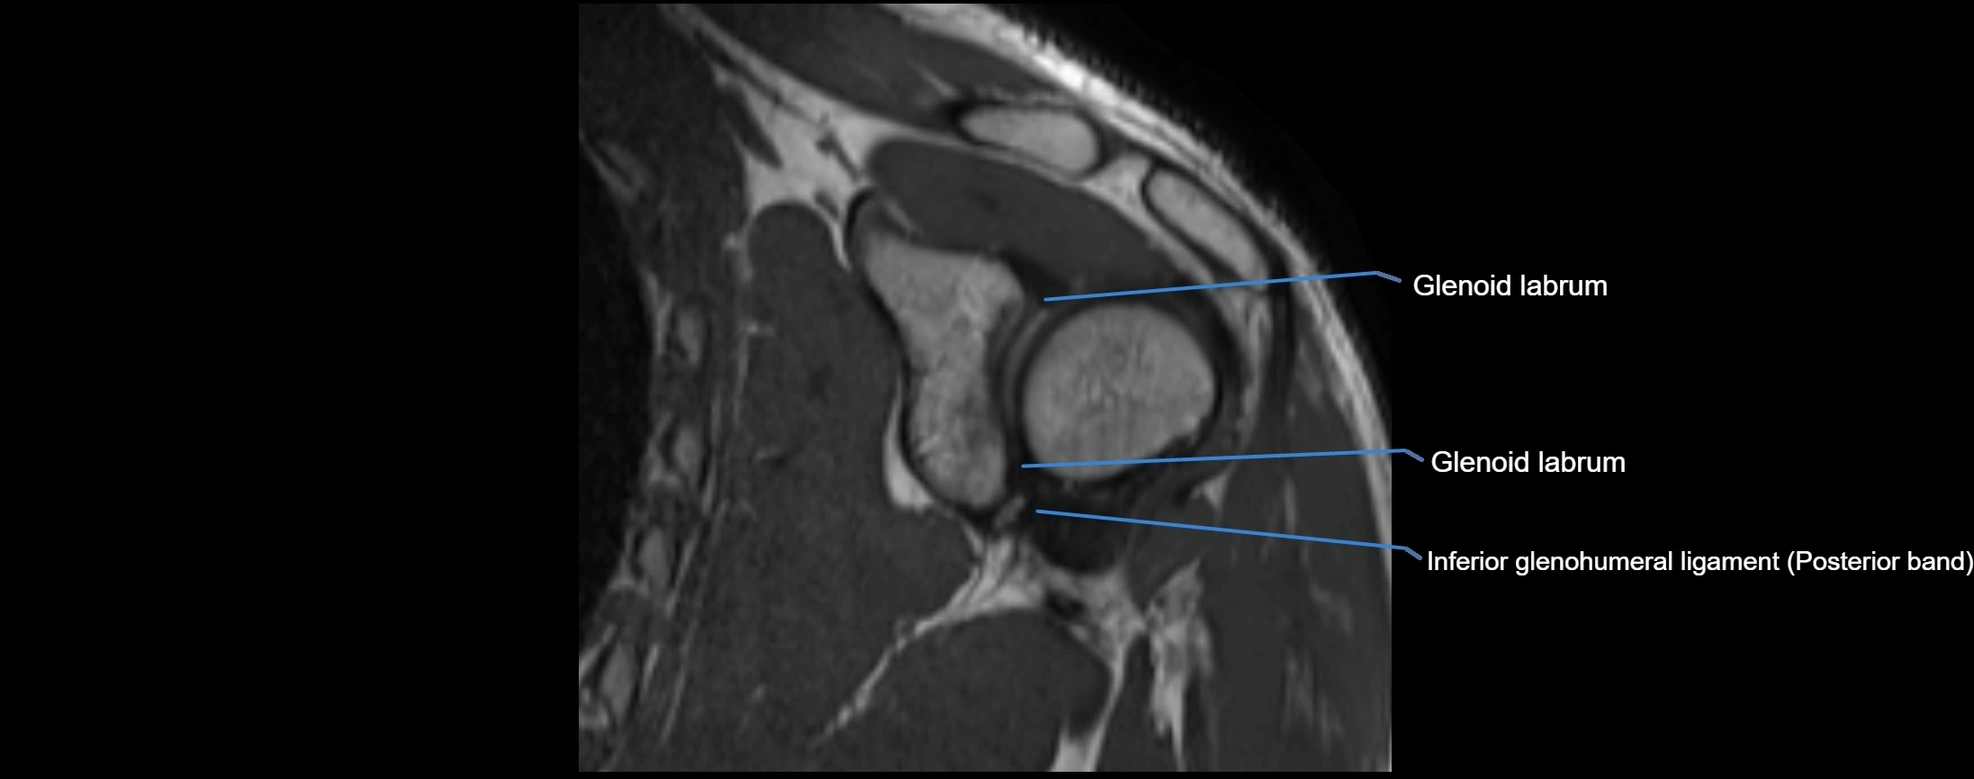

MRI Appearance

• T1-weighted images:

• Normal ligament: Low signal (dark linear band) spanning acromion to clavicle.

• Surrounding fat planes: Bright, delineating the ligament clearly.

• Marrow of clavicle and acromion: Bright due to fatty content.

• Tears: Discontinuity or irregular thickening with intermediate-to-bright signal.

• Chronic injury: Thinning, fraying, or irregular low-signal fibers with adjacent scarring.

• T2-weighted images:

• Normal ligament: Low signal, homogeneous.

• Partial tear or sprain: Focal hyperintensity or thickening.

• Complete tear: Discontinuity with fluid-bright gap between clavicle and acromion.

• Associated edema: Bright signal in distal clavicle or acromion marrow.

MRI images

image